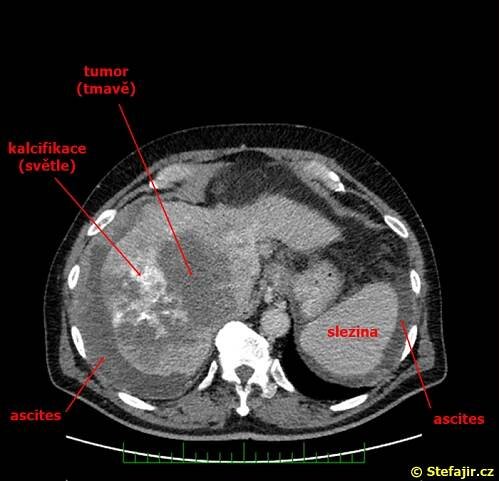

Hepatocelulární karcinom (HCC) je nejčastější primární maligní nádor jater. Celosvětově je hepatocelulární karcinom pátým nejčastějším nádorem u mužů a osmým u žen. K rozvoji tohoto karcinomu dochází nejčastěji u pacientů s chronickým jaterním onemocněním, obvykle v terénu cirhózy různé etiologie…

Hepatocelulární karcinom (HCC) je nejčastějším primárním maligním nádorovým onemocněním jater. Podle údajů systému Globocan bylo na celém světě v roce 2018 registrováno 841 080 případů HCC, ve stejném roce a podle stejného zdroje bylo…